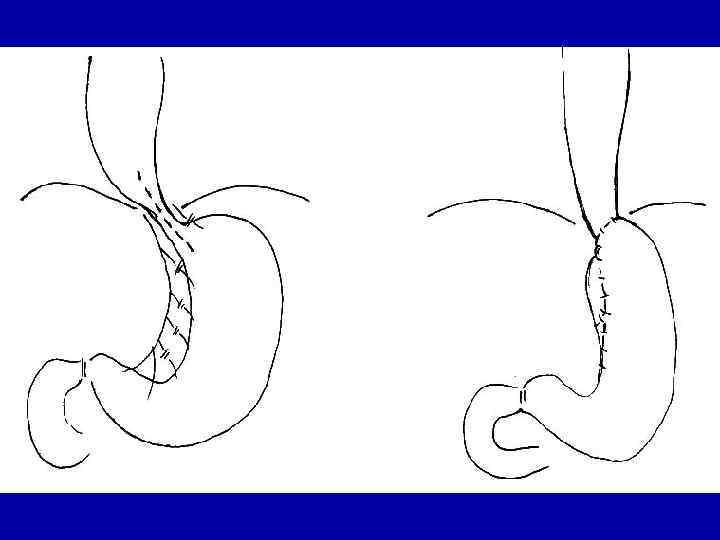

Схема внутриплевральной пластики пищевода желудочной трубкой